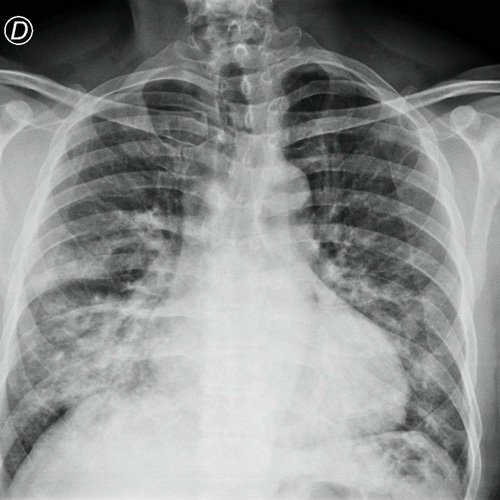

Radiografía de tórax frente y perfil

• Radiografía de tórax frente/perfil (Dia 0): rotada, bien inspirada,  índice cardiotorácico impresiona conservado , se observa infiltrado parenquimatoso a nivel medio basal de campo pulmonar derecho e izquierdo,   senos costofrénicos impresionan libres..